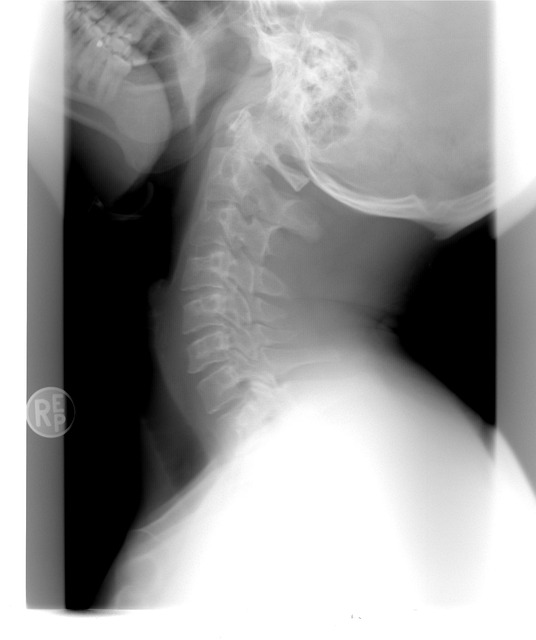

관절염은 염증이 관절에 생기는 질환이에요.

📌 특히 무릎·손가락 관절염은 체중이 늘거나 영양 균형이 깨지면 더 악화되기 쉬워요.